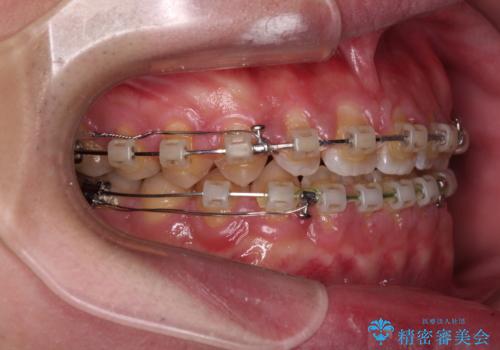

- クリアブラケット

舌の突出癖がなかなか改善されず、治療期間は当初予定よりも大分長くなりました。

装置除去を予定していた日に、油断されたのか1mmほどのスペースを作ってしまったため、除去が3ヶ月延長されたことで、舌のトレーニングの重要性を理解していただきました。

装置除去後もトレーニングを継続されているようで、後戻りによるスペースは今のところ認められておりません。